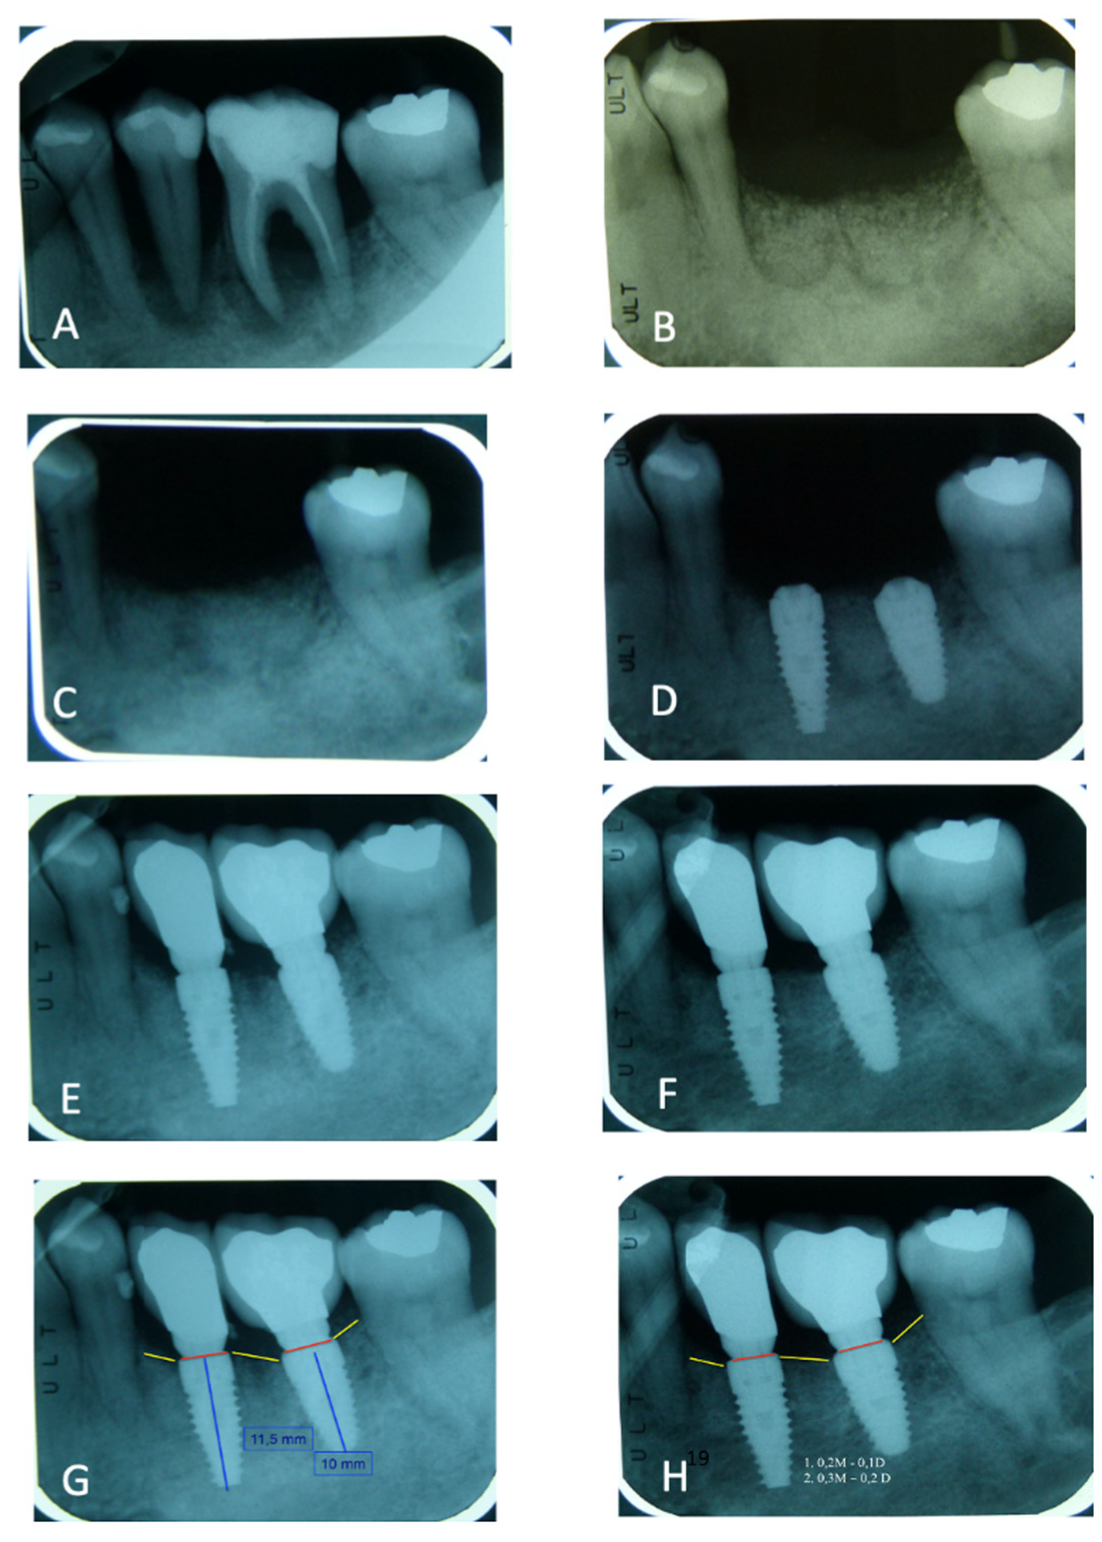

3.1. Peri-Implant Bone Loss Evaluation

3.4. Peri-Implant Bone Loss

| Average Implant Length | 10.83mm (±1.17) |